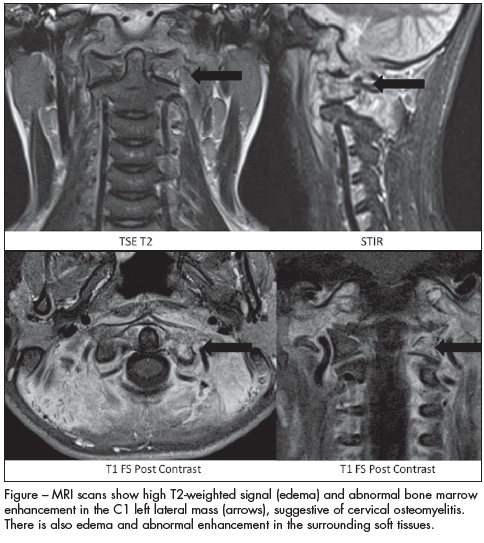

osteomyelitis

Ronald B. Turner, MD; Gregory F. Hayden, MD; Nathan T. Cohen, MD, BS; Talissa A. Altes, MD

A 9-year-old girl was transferred from an outside hospital because of neck pain with associated fever.